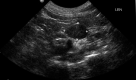

Diagnostics: In any cat presenting with hypokalaemia and/or arterial hypertension, other potential causes should be excluded. The ratio of plasma aldosterone concentration to plasma renin activity (aldosterone:renin ratio) is currently the best screening test for feline primary hyperaldosteronism. Diagnostic imaging is required to differentiate between adrenocortical neoplasia and bilateral hyperplasia, and to detect any distant metastases.

Clinical challenges: The differentiation between adrenocortical neoplasia and bilateral hyperplasia is imperative for planning optimal therapy, but the limited sensitivity of diagnostic imaging may occasionally pose a problem. For confirmed unilateral primary hyperaldosteronism, unilateral adrenalectomy is the treatment of choice, and offers an excellent prognosis, but potentially fatal intra- and postoperative haemorrhage is a reported complication and risk factors have yet to be identified.